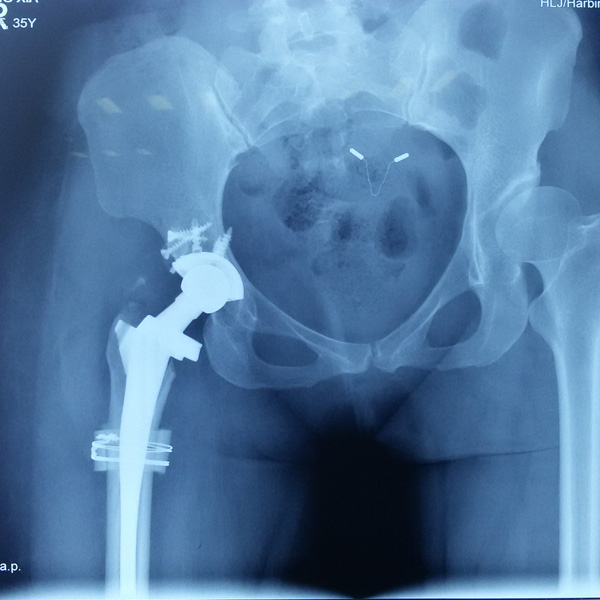

先天性髖關(guān)節(jié)脫位

患者王某某,女,41歲,從會(huì)走路以來就發(fā)現(xiàn)一條腿長(zhǎng),一條腿短,也就是人們俗稱的“跛子”,之前雖然兩條腿長(zhǎng)短不一,但起碼還可以走路,維......